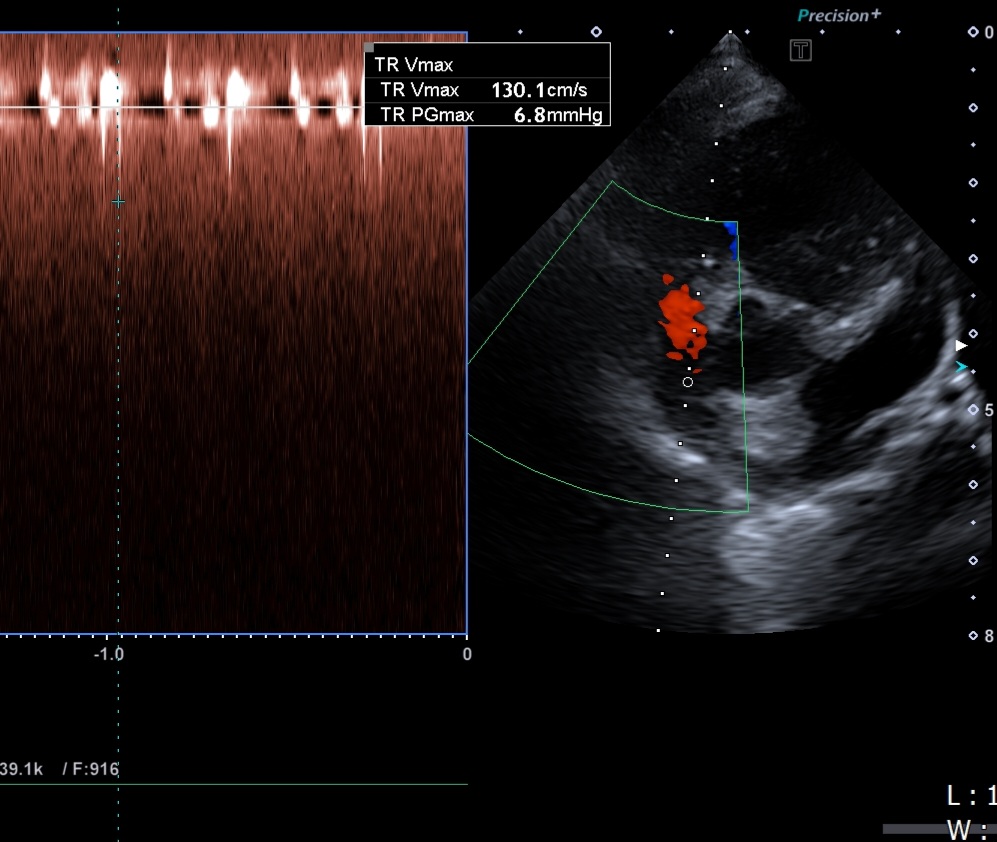

강아지의 승모판 폐쇄부전증 이란? 강아지의 승모판 폐쇄부전증은 심장의 좌심방과 좌심실 사이에 위치한 **승모판(mitral valve)**이 제대로 닫히지 않아 혈액이 역류하는 질환이다. 이는 강아지 심장질환 중 가장 흔한 형태로, 특히 노령 소형견에서 매우 높은 빈도로 발생한다.이 질환은 진행성(degenerative)인 특성을 가지며, 시간이 지날수록 심부전(congestive heart failure)으로 악화될 수 있다.원인과 발생 위험군주된 원인은 노화에 따른 승모판 구조의 변성이다.판막이 두꺼워지거나, 탄력을 잃고 물결치듯 휘어지면서 정상적인 개폐 작용이 어려워지며 역류가 발생한다.고위험군7세 이상의 노령견말티즈, 푸들, 치와와, 요크셔테리어, 시츄 등의 소형견유전적 요인도 관여 가능병리기전 ..